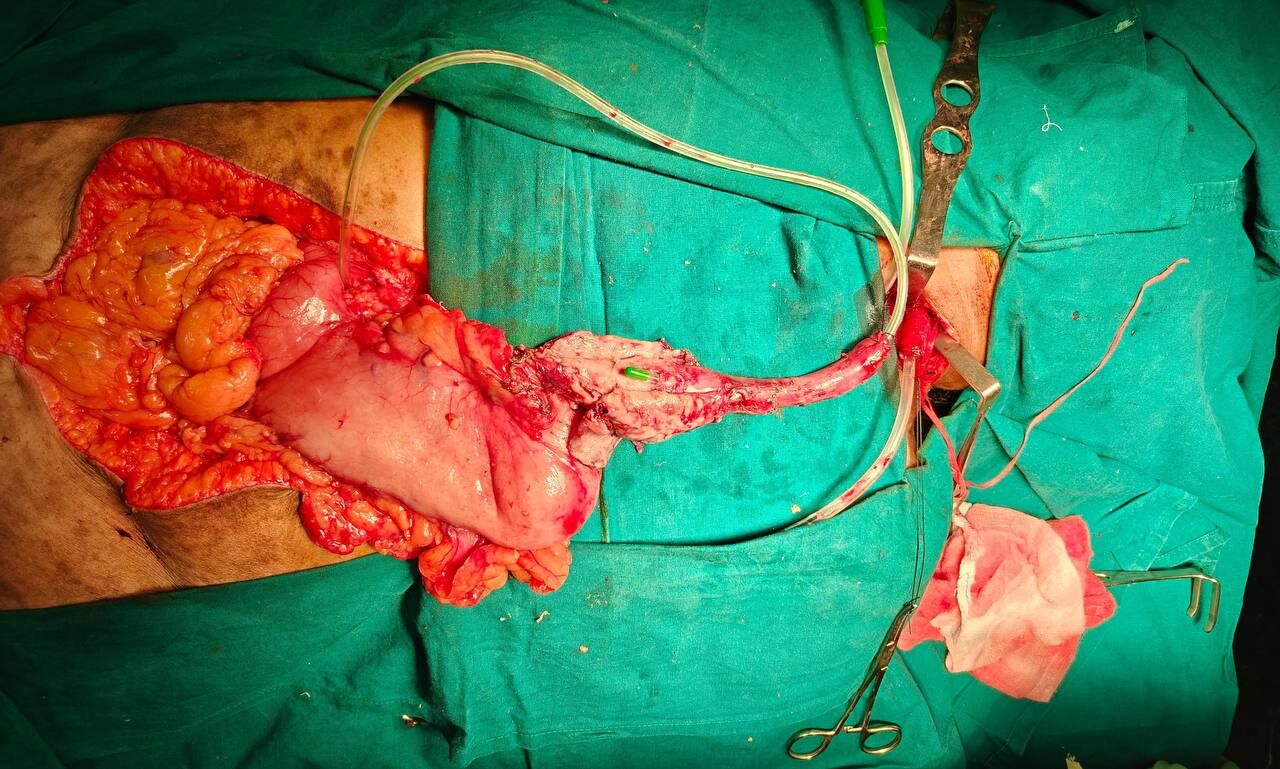

A 68-year-old female with squamous cell carcinoma of the lower esophagus (cT3N0M0) developed an iatrogenic esophageal perforation following endoscopy, leading to mediastinitis.

The patient was initially managed conservatively. An attempt at endoscopic stenting was made; however, stent placement was not feasible as the distal lumen could not be identified endoscopically. By day 3, in view of worsening mediastinitis and a large perforation involving more than 50% of the esophageal circumference, a decision was made to proceed with surgical exploration.

Given that the patient remained hemodynamically stable but showed progression of local sepsis, she underwent an emergency transthoracic esophagectomy with gastric conduit reconstruction. The procedure allowed definitive control of the source of contamination and restoration of gastrointestinal continuity.